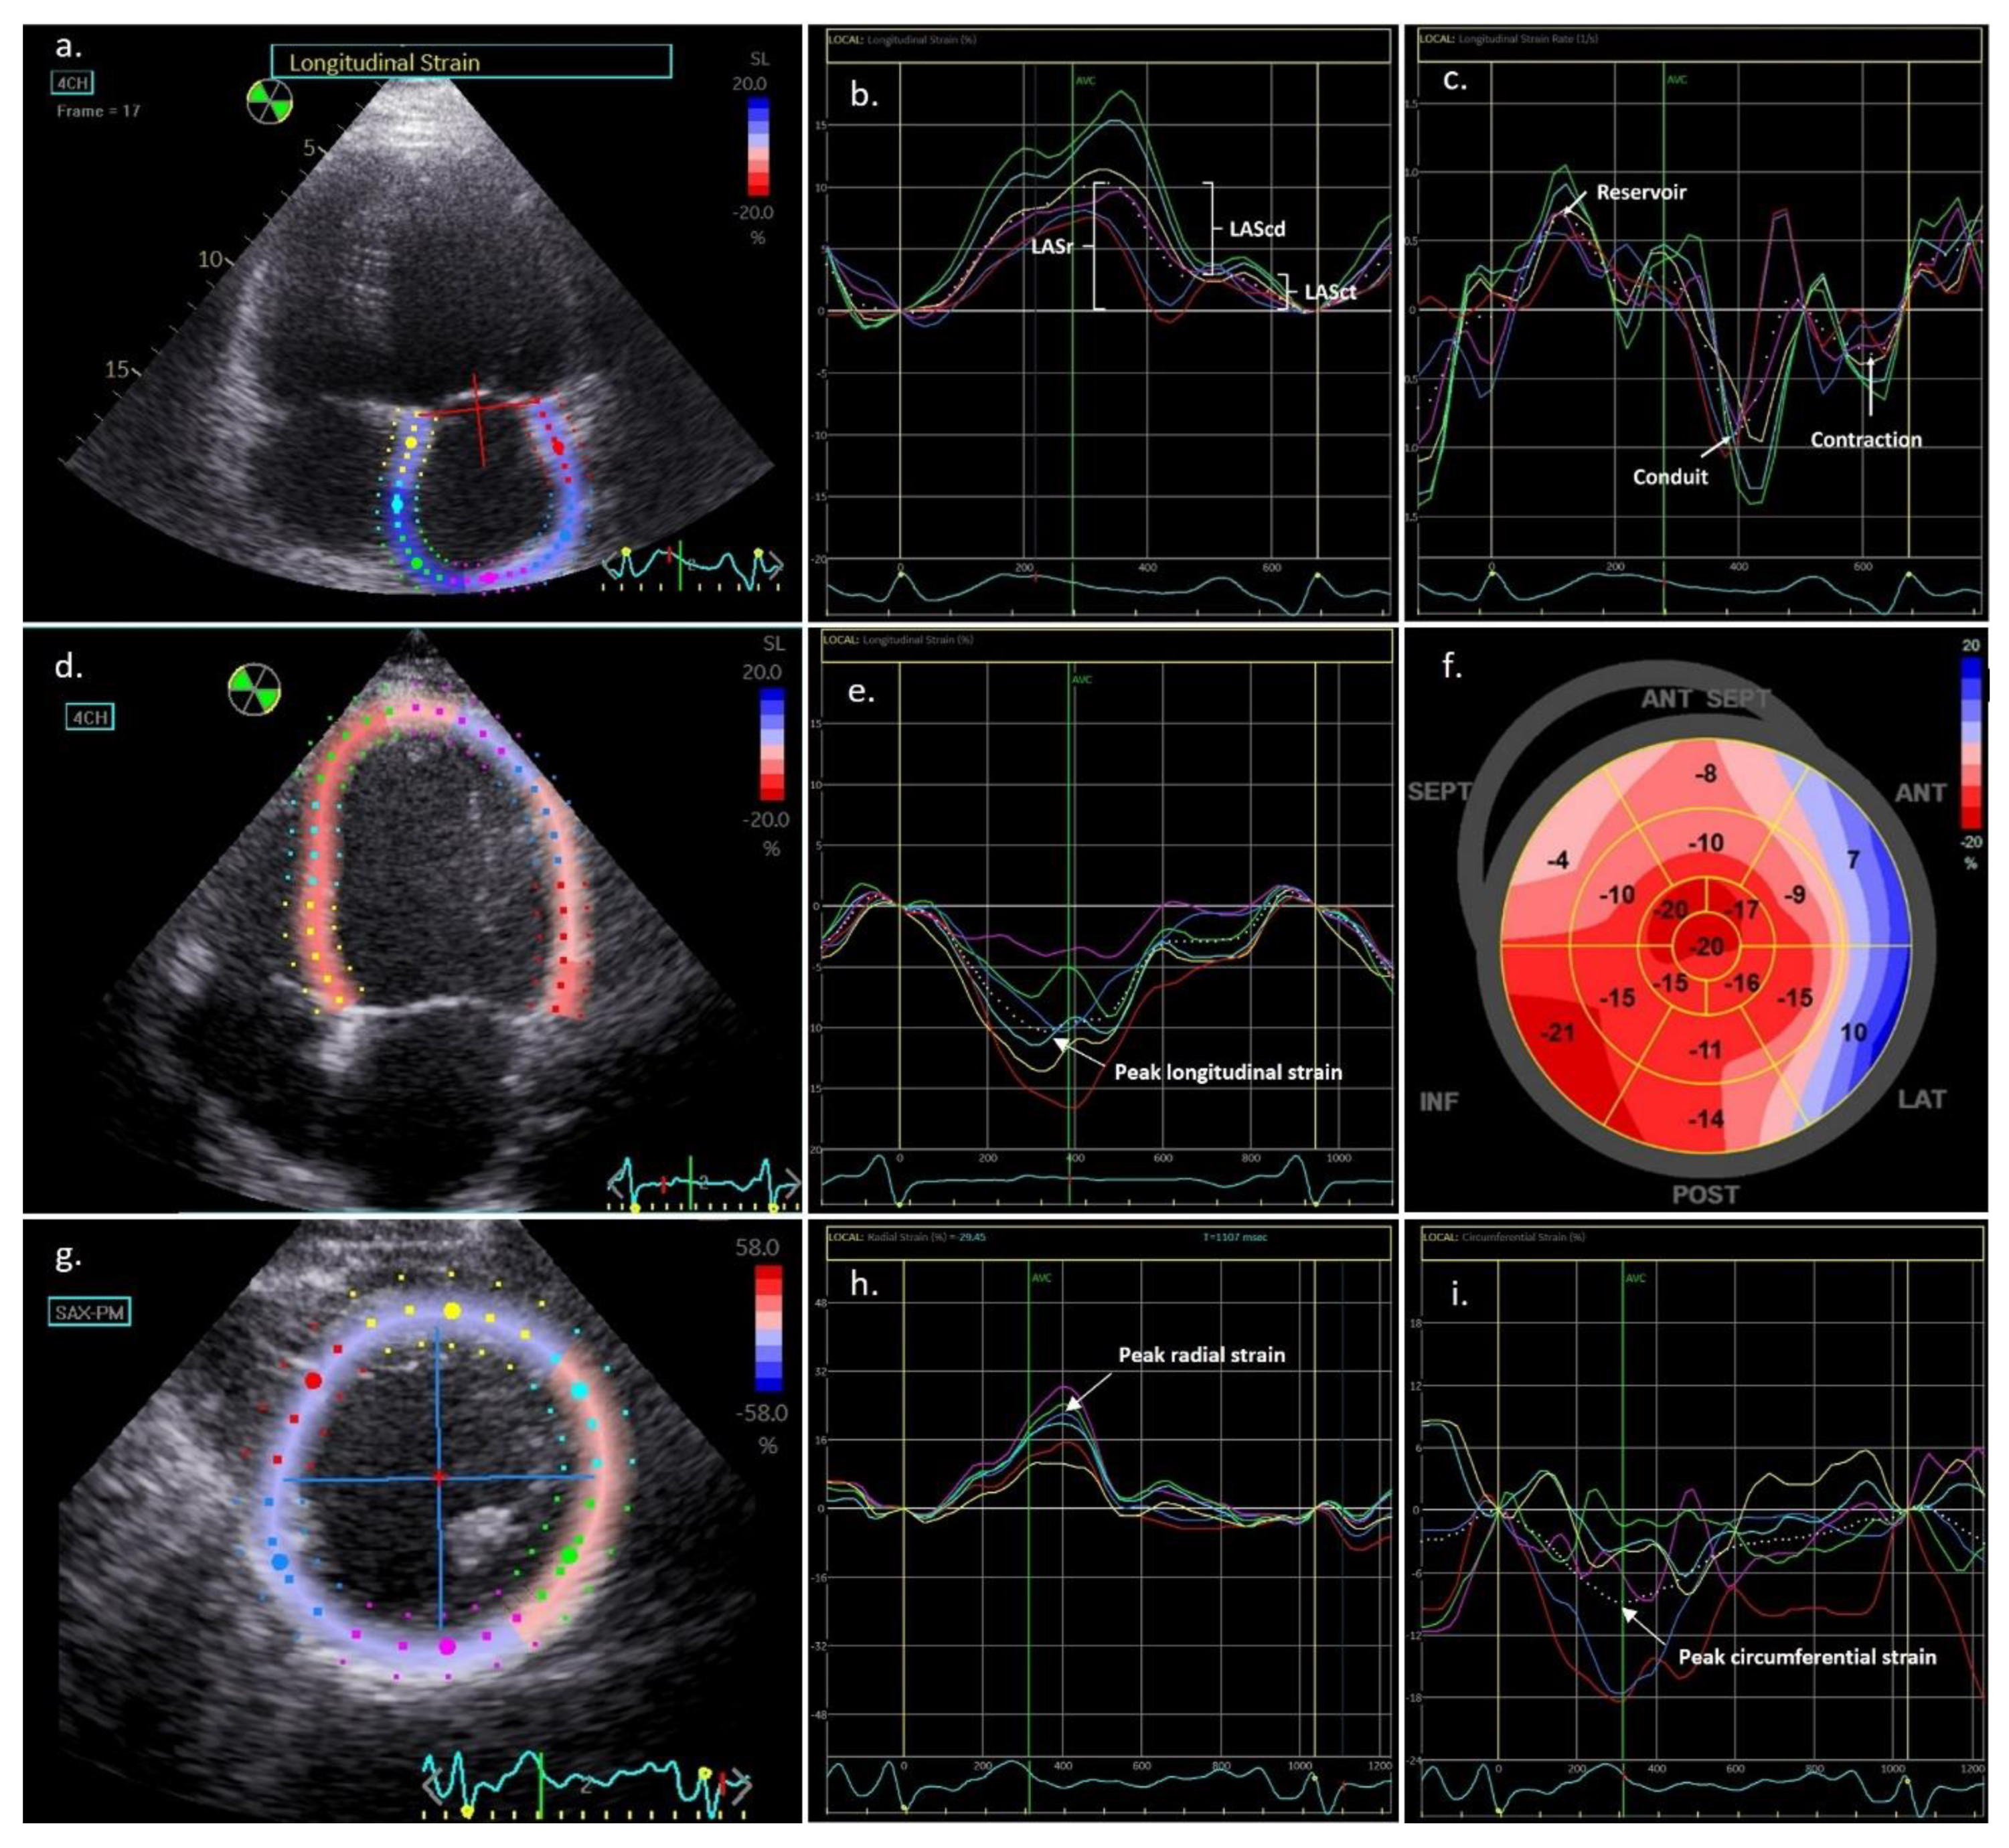

3.5.1. LA Strain Assessment

3.5.2. LV strain Assessment

| Left atrial strain parameters | |||

| LA strain reservoir (%) | 11.5 ± 6.2 | 16.1 ± 7.8 | <0.001 |

| LA strain conduit (%) | −6.3 [−8.5–−4.4] | −7.4 [−11.4–−5.0] | 0.003 |

| LA strain contraction (%) * | −7.2 ± 4.1 | −10.9 ± 3.9 | 0.003 |

| LA strain rate reservoir (s−1) | 0.49 ± 0.22 | 0.65 ± 0.22 | <0.001 |

| LA strain rate conduit (s−1) | −0.47 [−0.68–−0.29] | −0.58 [−0.87–−0.39] | 0.018 |

| LA strain rate contraction (s−1) * | −0.82 [−1.14–−0.47] | −1.08 [−1.48–−0.94] | 0.018 |

| Left ventricular strain parameters | |||

| Global longitudinal strain (%) | −7.0 ± 2.6 | −8.9 ± 2.8 | 0.001 |

| Peak longitudinal strain (%) | −5.6 ± 2.0 | −9.3 ± 2.7 | <0.001 |

| Longitudinal systolic strain rate (s−1) | −0.32 ± 0.11 | −0.47 ± 0.14 | <0.001 |

| Longitudinal early diastolic strain rate (s−1) | 0.25 [0.18–0.41] | 0.46 [0.27–0.62] | <0.001 |

| Longitudinal late diastolic strain rate (s−1) * | 0.31 ± 0.17 | 0.44 ± 0.19 | 0.002 |

| Peak radial strain (%) | 5.9 [4.3–9.2] | 11.7 [7.7–14.7] | <0.001 |

| Radial systolic strain rate (s−1) | 0.66 ± 0.26 | 0.90 ± 0.30 | 0.001 |

| Radial early diastolic strain rate (s−1) | −0.54 ± 0.48 | −0.95 ± 0.72 | 0.001 |

| Radial late diastolic strain rate (s−1) * | −0.58 [−0.86–−0.37] | −0.71 [−1.20–−0.51] | 0.061 |

| Peak circumferential strain (%) | −7.7 ± 2.3 | −9.9 ± 2.5 | 0.001 |

| Circumferential systolic strain rate (s−1) | −0.78 [−0.97–−0.58] | −0.87 [−1.10–−0.73] | 0.026 |

| Circumferential early diastolic strain rate (s−1) | 0.87 ± 0.24 | 0.95 ± 0.21 | 0.102 |

| Circumferential late diastolic strain rate (s−1) * | 0.48 [0.34–0.78] | 0.59 [0.50–0.82] | 0.041 |